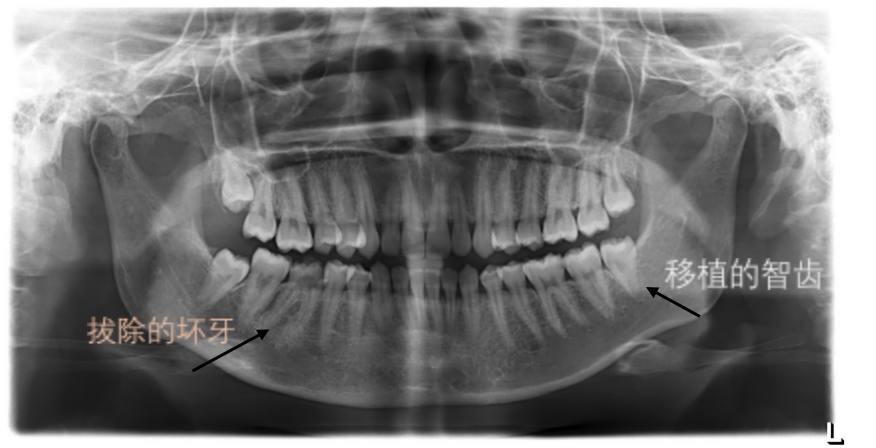

术前照片

术后照片